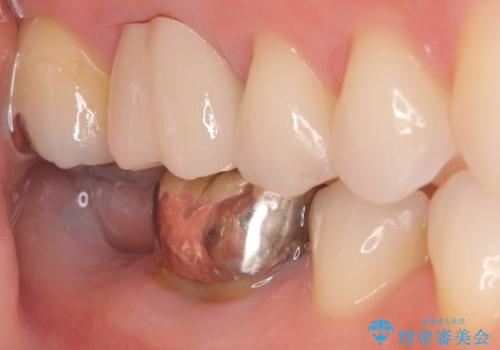

- 患者様は、奥歯を失ったことで「しっかり噛めるようになりたい」とのご希望で来院されました。ブリッジや入れ歯ではなく、インプラントによる治療を希望されたため、精密検査を実施。骨の状態が良好であったため、1回法(1回の手術でインプラント埋入とヒーリングアバットメント装着を同時に行う方法)を選択しました。これにより、外科的負担を軽減しながら、治療期間の短縮も図ることができました。

手術は1回で完了し、局所麻酔下でインプラントを埋入した後、ヒーリングアバットメントを装着。術後の腫れや痛みも少なく、患者様はスムーズに日常生活へ戻ることができました。約3ヶ月の治癒期間を経て、セラミッククラウンをセット。見た目の美しさはもちろん、天然歯に近い噛み心地を実現しました。患者様からは「違和感なくしっかり噛める」とご満足の声をいただきました。